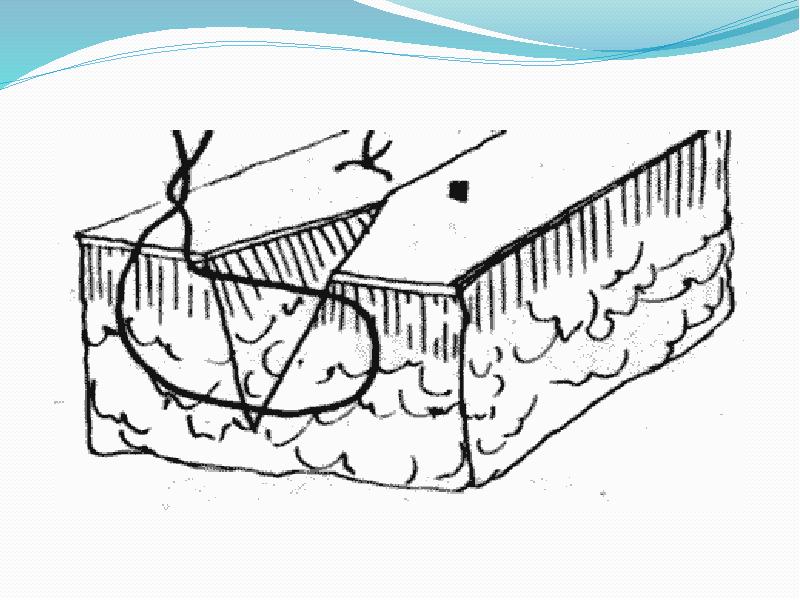

- 36. Шов Спасокукоцкого